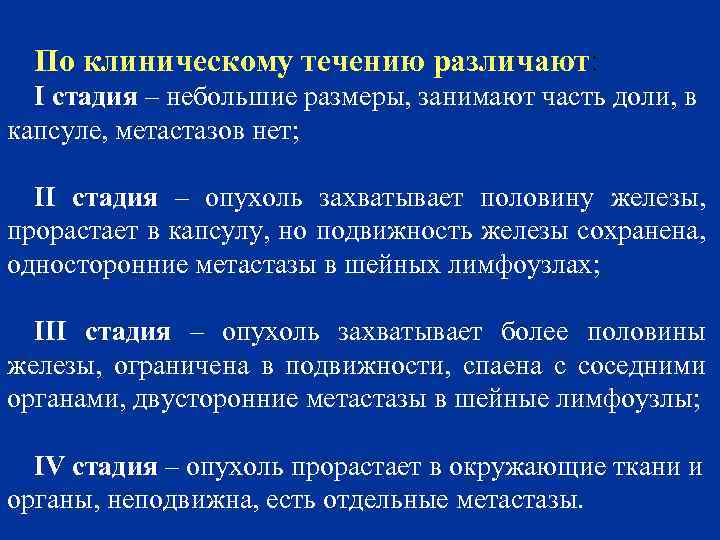

По клиническому течению различают: I стадия – небольшие размеры, занимают часть доли, в капсуле, метастазов нет; II стадия – опухоль захватывает половину железы, прорастает в капсулу, но подвижность железы сохранена, односторонние метастазы в шейных лимфоузлах; III стадия – опухоль захватывает более половины железы, ограничена в подвижности, спаена с соседними органами, двусторонние метастазы в шейные лимфоузлы; IV стадия – опухоль прорастает в окружающие ткани и органы, неподвижна, есть отдельные метастазы.

По клиническому течению различают: I стадия – небольшие размеры, занимают часть доли, в капсуле, метастазов нет; II стадия – опухоль захватывает половину железы, прорастает в капсулу, но подвижность железы сохранена, односторонние метастазы в шейных лимфоузлах; III стадия – опухоль захватывает более половины железы, ограничена в подвижности, спаена с соседними органами, двусторонние метастазы в шейные лимфоузлы; IV стадия – опухоль прорастает в окружающие ткани и органы, неподвижна, есть отдельные метастазы.